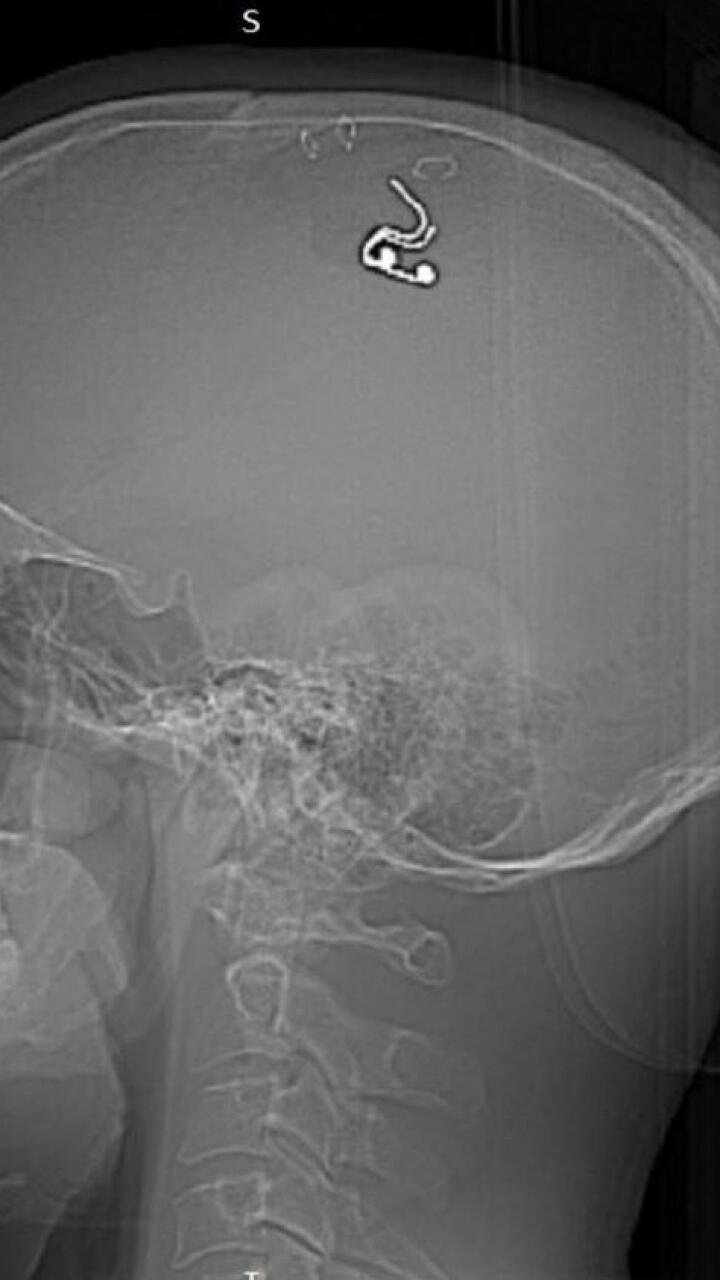

Hombre se perforó el cráneo para poder “controlar los sueños”

Michael Raduga, un investigador de 40 años que nació en Rusia, estuvo a punto de morir luego de que se practicara una cirugía cerebral a sí mismo.

Según una publicación en su cuenta de Instagram, lo que buscaba con este “experimento” era colocarse un implante cerebral para tener sueños lúcidos.

Este sujeto, quien no tiene conocimientos en neurocirugía o medicina, de acuerdo con el medio Daily Mail, logró sobrevivir a la implantación de un electrodo (una varilla metálica).

Explicó que utilizó un taladro que compró en la ferretería para perforarse el cráneo y así quitar una parte de este.

Después de cinco semanas de haberse perforado, un grupo médico extrajo el implante cerebral.